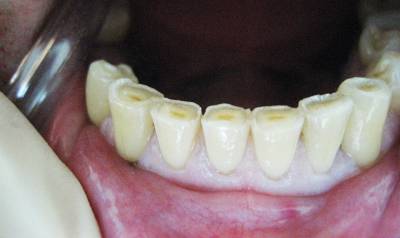

Существует особая классификация данной патологии, которая разделяется по глубине поражения, по стадии развития, по плоскости поражения и по ее протяженности.При патологической стираемости жёстких тканей зуба, идет сперва стираемость эмали, а позже дентина.

Так как эмаль более прочная структура, ее стирание идет на большое количество продолжительнее, чем стирание дентина, исходя из этого, в то время, когда происходит обнажение дентина, зуб утрачивает собственный количество на большое количество стремительнее. При, для того чтобы рода стираемости образуются острые края, каковые смогут причинять больному неудобства, травмируя слизистую и язык.

Так же, существенно страдает эстетический вид, не говоря уже о функциональных нарушениях. Если не проводится никакого лечения, то большим образом страдает ВНЧС (височно-нижнечелюстной сустав), появляются боли в его области, страдает слух.

По глубине поражения различают три степени:В-четвертых, неправильные конструкции зубных протезов, так же смогут привести к излишнему стиранию жёстких тканей зуба.Первая степень характеризуется оголением дентина и полным стиранием эмали, не доходящее до экватора.Повышенная стадия проявляется в пределах дентина.